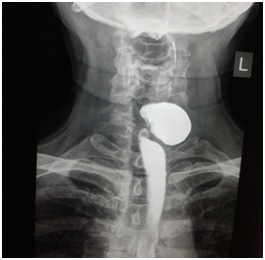

All six patients were symptomatic Four of patients were male. Age of patients was 65 to 80years. Four of patients came with dysphasia aspiration, halitosis, and malnutrition and regurgitation, one of this patient present three period with aspiration pneumonia and hospital admission. One of patients underwent endoscopic diverticulotomy and 24 hour after this procedure present with odynophagia, fever and neck subcutaneous emphysema With B-swallow perforation of diverticula was demonstrated, this patient underwent neck exploration and diverticulectomy and drainage. Diagnostic tools of five cases was B-swallow and esophagoscopy (Figures 1-5). One came with food marital retention and pain and neck mass tender mass. One patients referred with erithem, redness and criptation of neck with diagnosis of diverticulitis (Figures 6 & 7). Two cases underwent flexible endoscopic diverticulotomy, one failed and another ones complicated with perforation. The most common surgical approaches was diverticulectomy and myotomy in four patients (Figures 8 & 9). Food debris was present in one patient (Figure 10). Two of patients underwent diverticulectomy without myotomy. Complication and mortalities were zero. In two years flow-up, Outcome was good.

Figure 2 Show swallow of a 85 year old woman with huge Zenker's diverticulum.